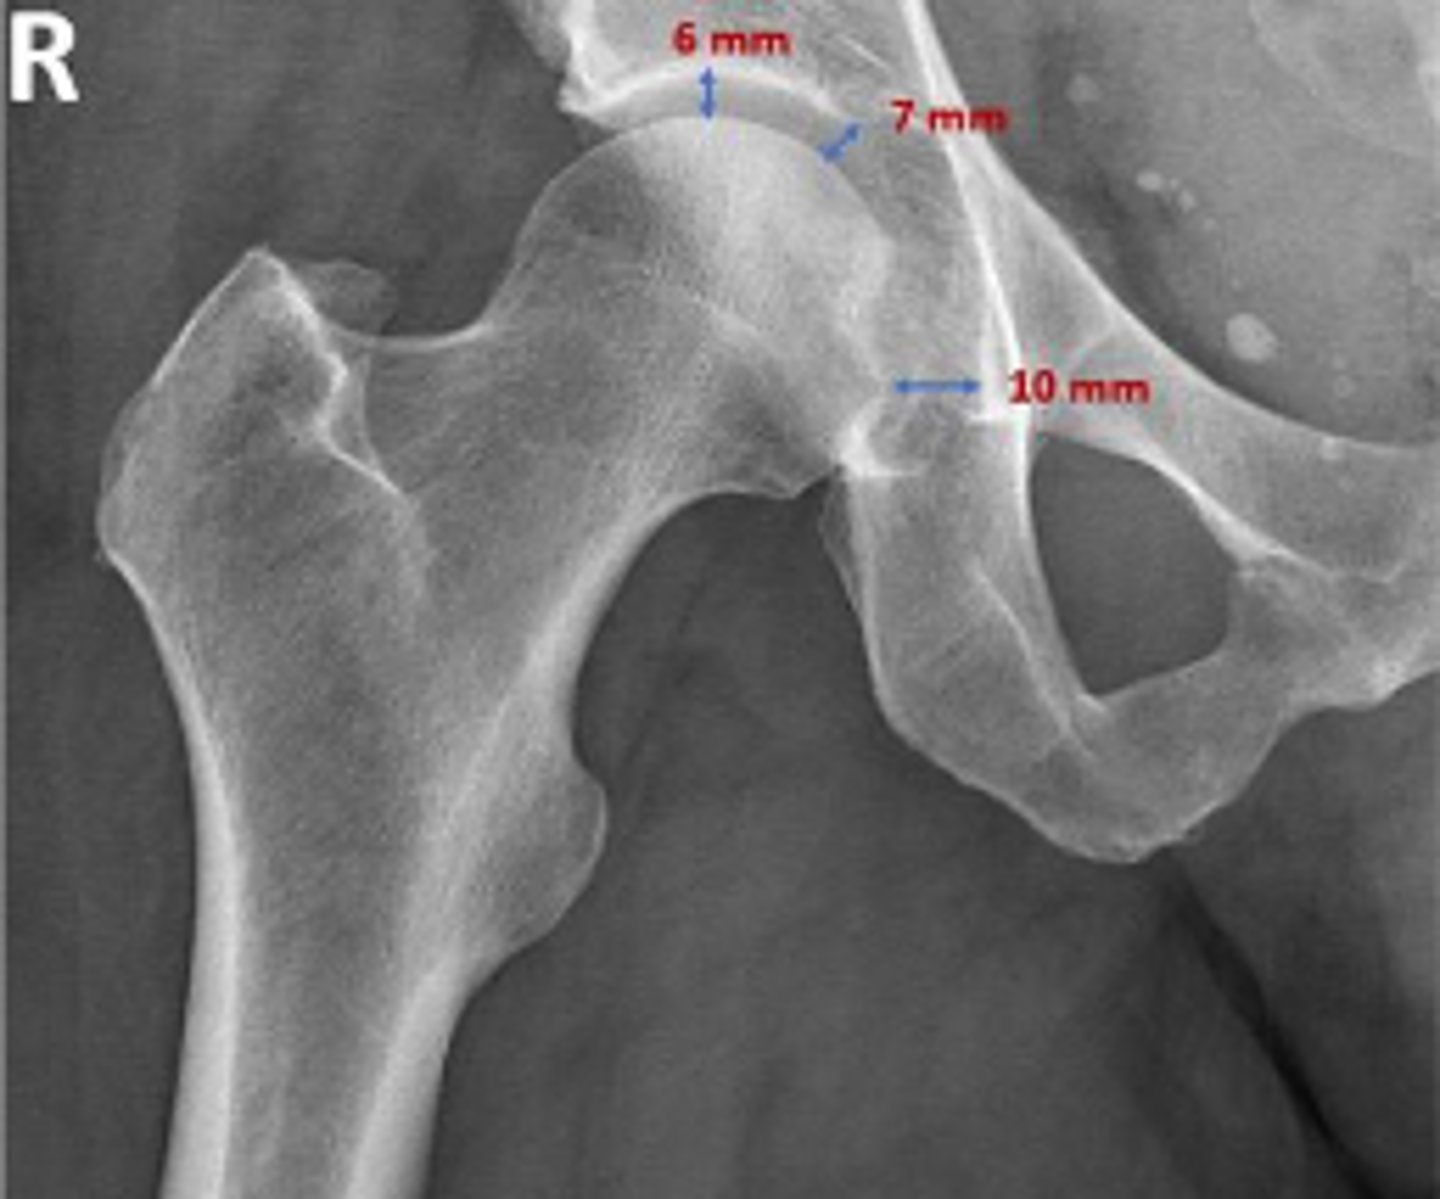

AP right hip

What is the radiographic view?

Hip joint space width

What is the name of the assessment?

Superior joint space is 3-6mm

Axial joint space is 3-7mm

Medial joint space is 4-13mm

What is the normal range for this assessment?

Superior joint space-> The measurement between the most convex superior aspect of the femoral head and the adjacent acetabulum

Axial joint space -> The measurement between the

femoral head and the acetabulum lateral to the

acetabular notch

Medial Joint space -> The measurement between the most medial margin of the femoral head and the adjacent pelvic teardrop

What are the osseous landmarks for this assessment?

Yes

Are the measurements within normal limits?

Degenerative joint disease

Name 1 condition that may result in a measurement of <3mm for the superior joint space?

AP pelvis and AP hip views

Name 2 radiographic views for this assessment?